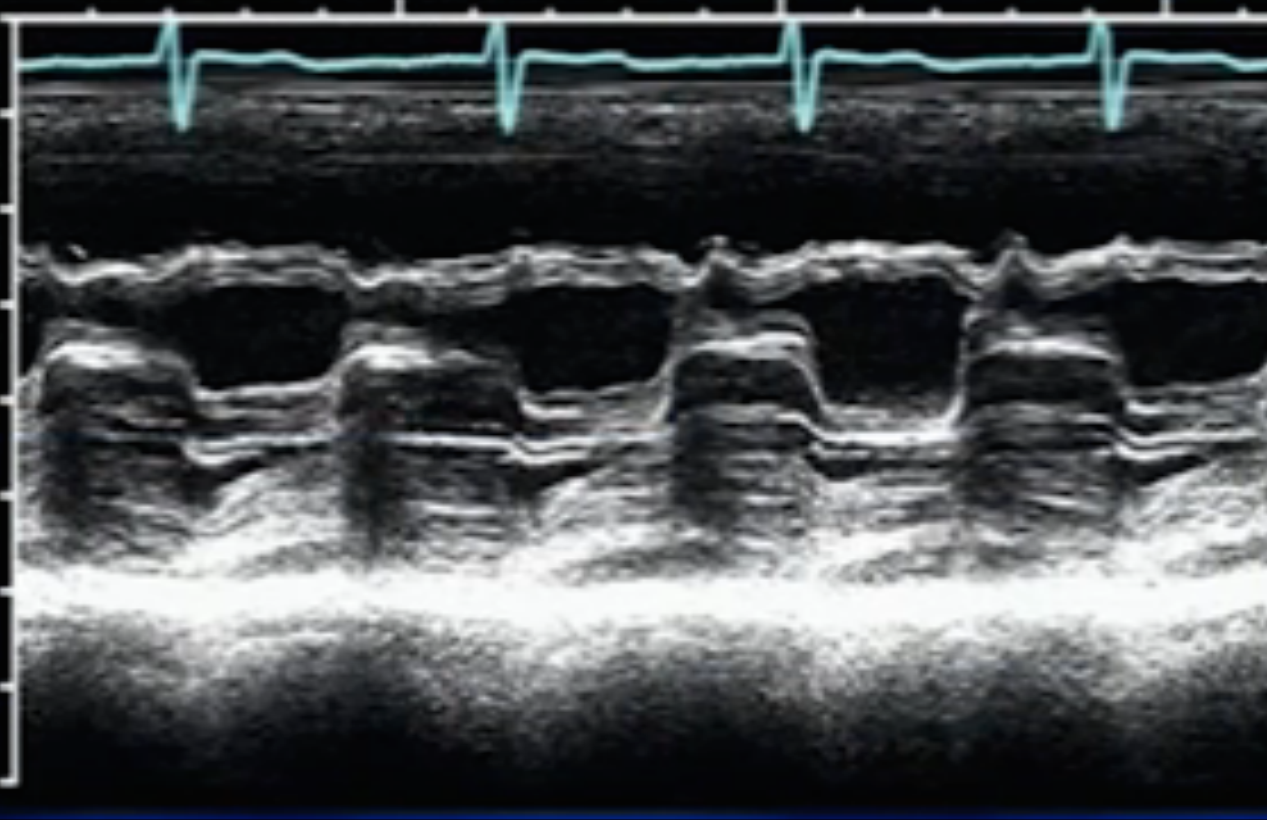

Diagnosis?

Constrictive Pericarditis (left shift of interventricular septum during inspiration)

Tamponade

(interventricular interdependence, see how the septum moves away from RV and dips towards LV on inspiration)